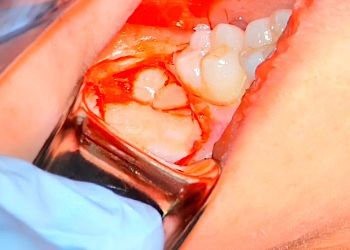

20 MODULES TO MASTER EXODONTIA

Everything you will ever need to know to master exodontia!

Raw, battle-tested tips and real cases from a real GP. MASTER IT WITH ME!